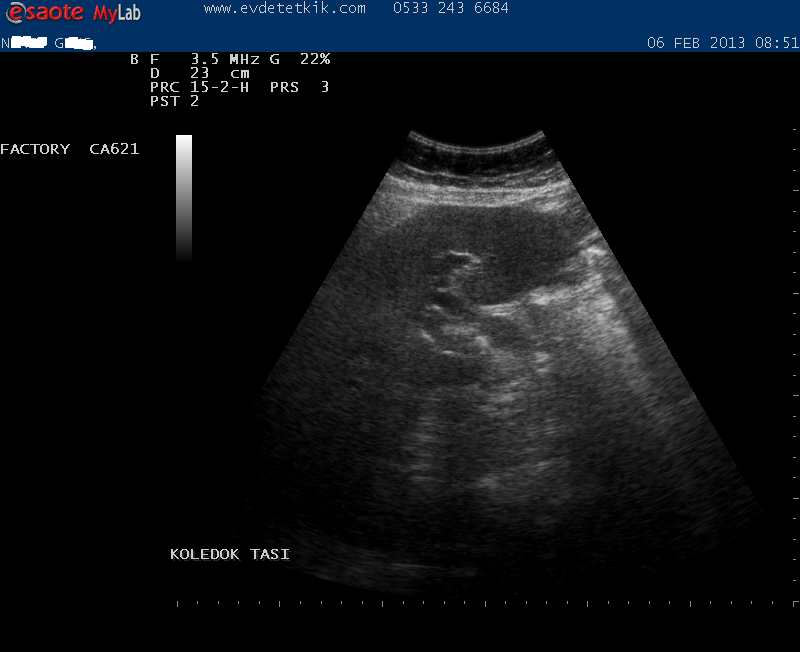

Hizmetimizden görüntüler